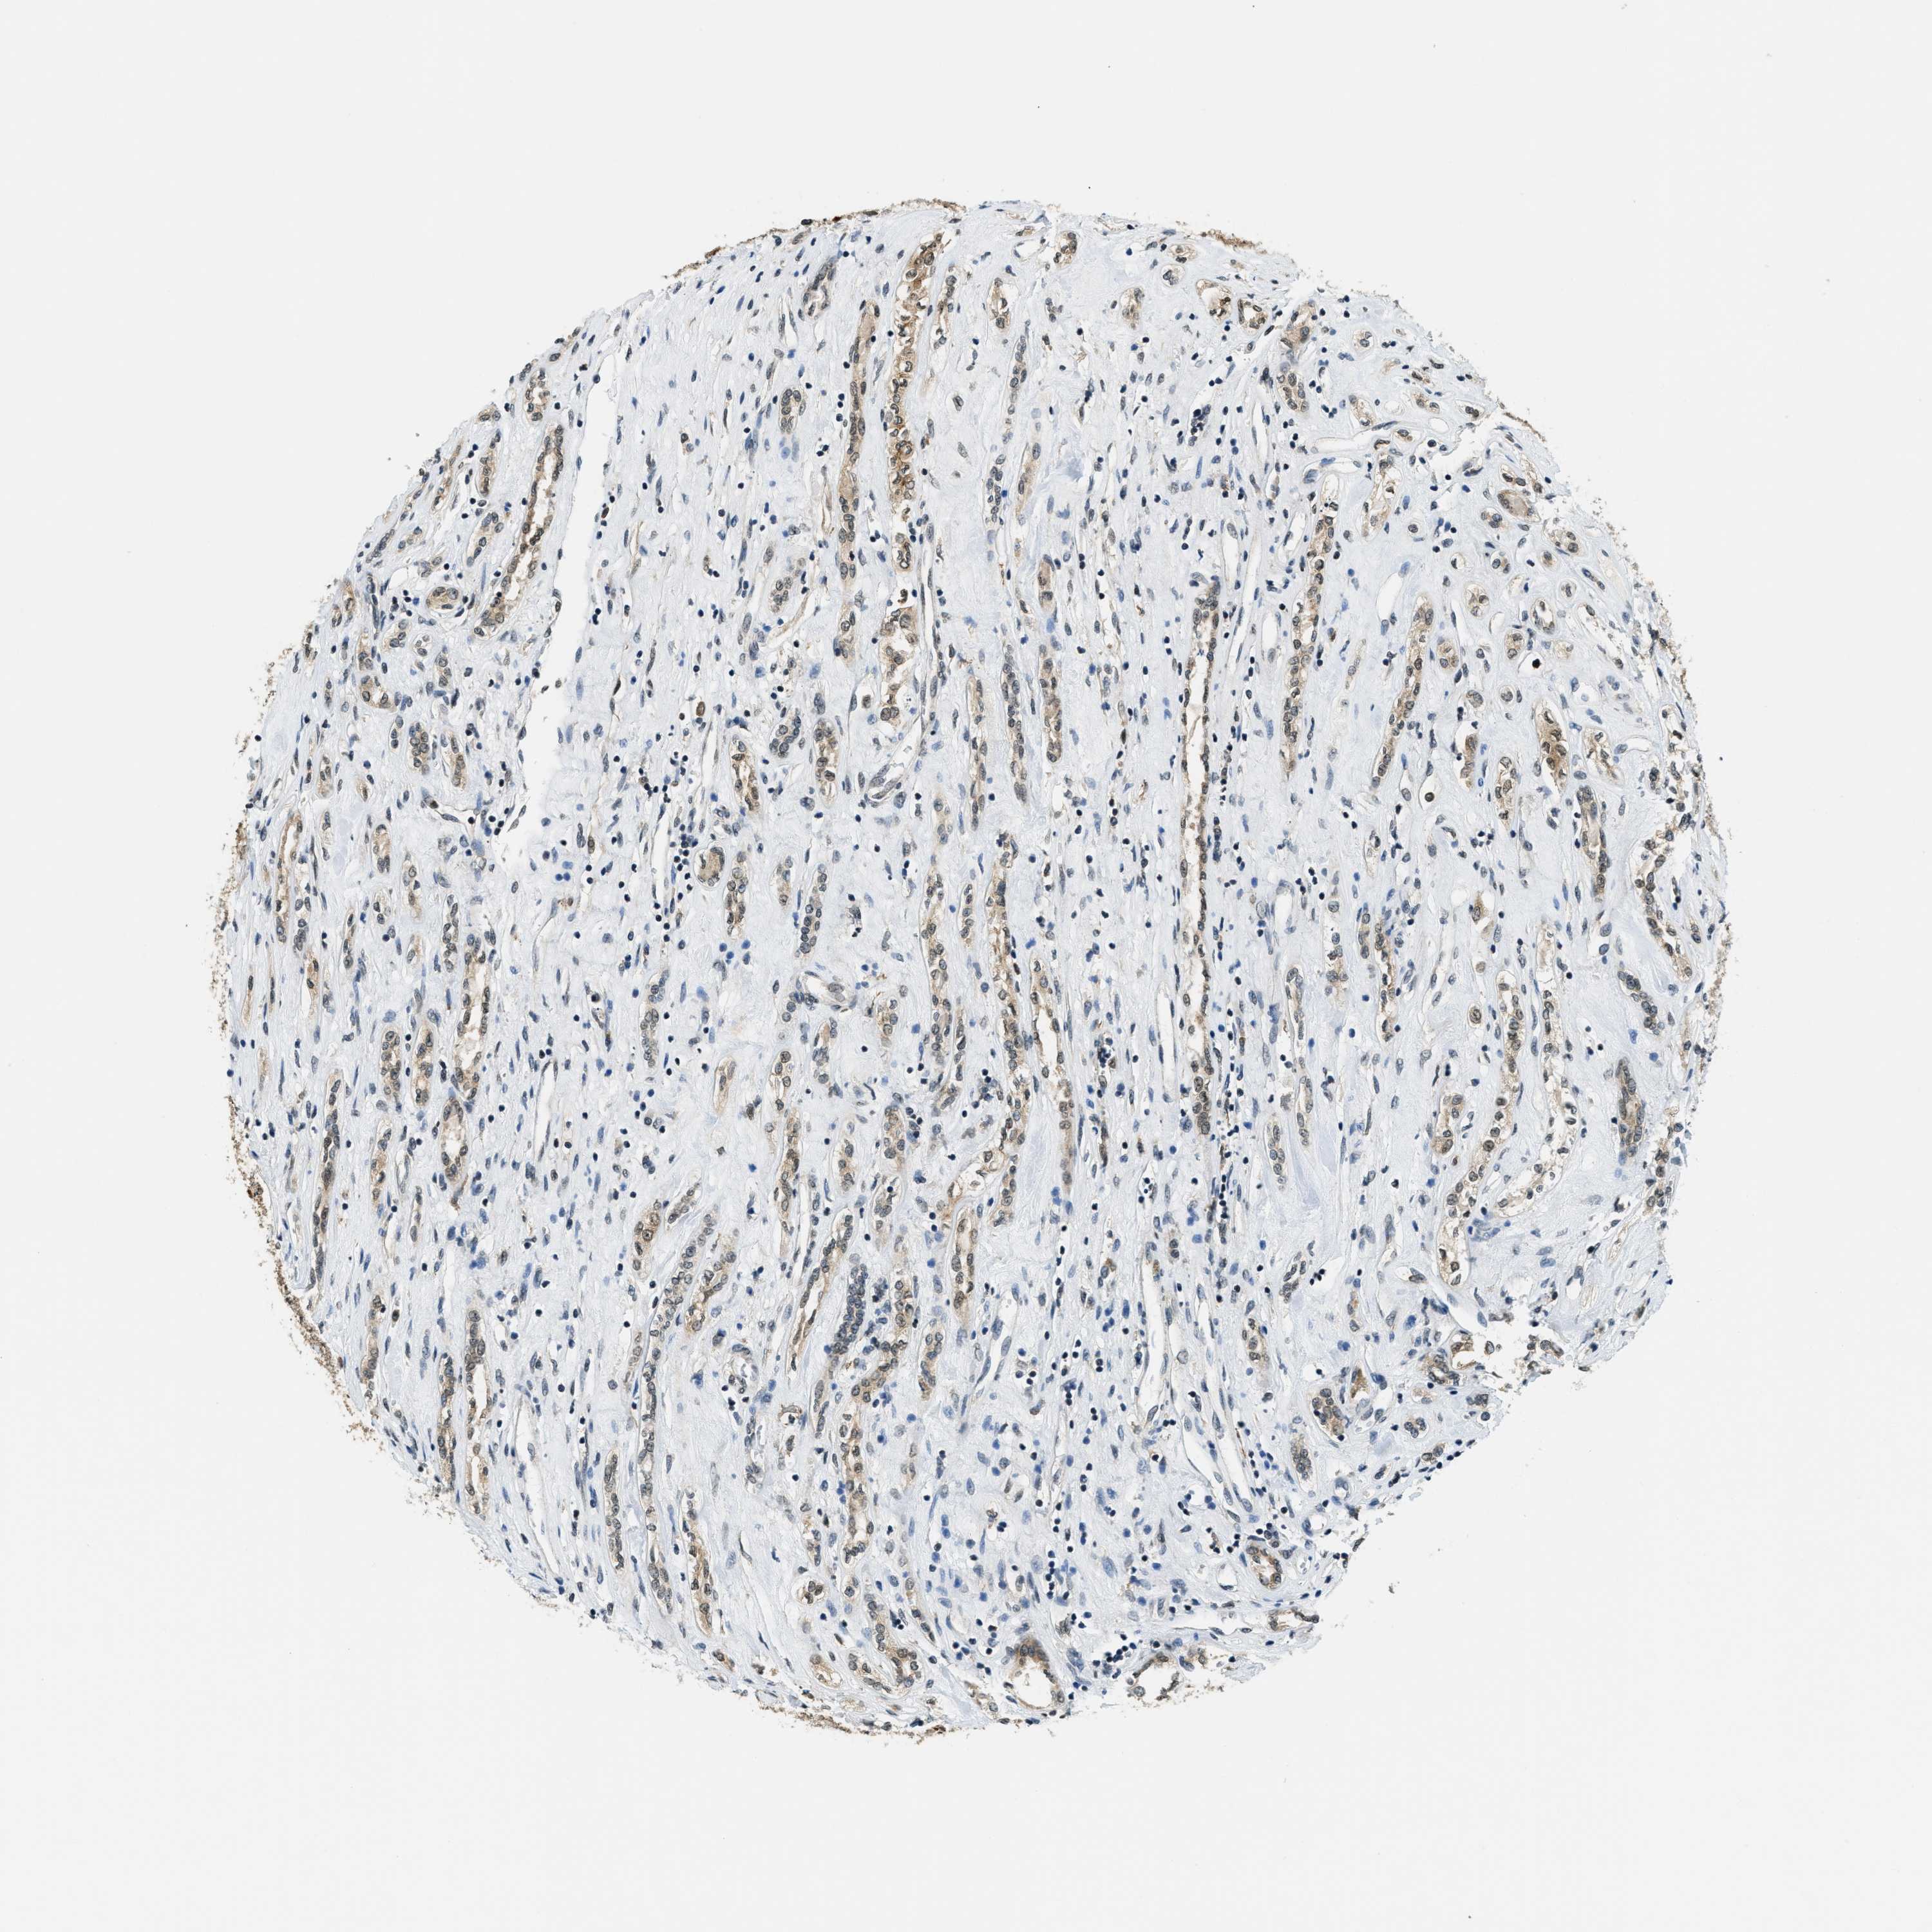

CANCER RENAL CANCER Show tissue menu

KICH TCGA KIRC TCGA KIRC VALIDATION KIRP TCGA PROTEIN RCC CPTAC PROTEIN EXPRESSION

Kidney renal papillary cell carcinoma